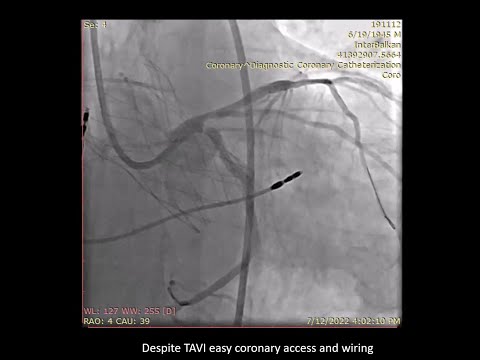

Left main (bifurcation) PCI using DK Crush technique through a Navitor TAVI